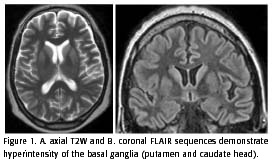

Recently, many authors reported cases of sCJD with typical findings at magnetic resonance imaging (MRI) in 67 to 79% of cases. The patients studied showed classic hyperintensity of the cerebral cortex and basal ganglia (putamen and caudate head) on T2-weighted images (T2W), FLAIR and diffusion-weighted (DWI) sequences, in both the early and late stages (more than 4 months after the onset of symptoms). This finding is indicative of restricted water diffusion and is seen mainly in the basal ganglia. The T1-weighted sequences are usually normal but may demonstrate slight hypointensity in the basal ganglia. The contrast enhancement does not occur (2, 4-10). According to these authors, these typical imaging findings, mainly the DWI findings, in conjunction with the classical clinical presentation, could facilitate the antemortem diagnosis of this rare entity.

The MRI was performed 3 months after the onset of symptoms and demonstrated marked hyperintensity in the basal ganglia on T2W, FLAIR and DWI sequences (Figure 1 and 2). Hyperintensity in the basal frontal cortex was also noted. The T1W images showed a faint hypointensity of the basal ganglia and no contrast enhancement. The apparent coefficient diffusion (ADC) in the striatum was 0,52 x 10-3 mm2/s (mean 0,74 ± 0,12 x 10-3 mm2/s in voluntary subjects, 64,9 ± 14,2 years) (5).